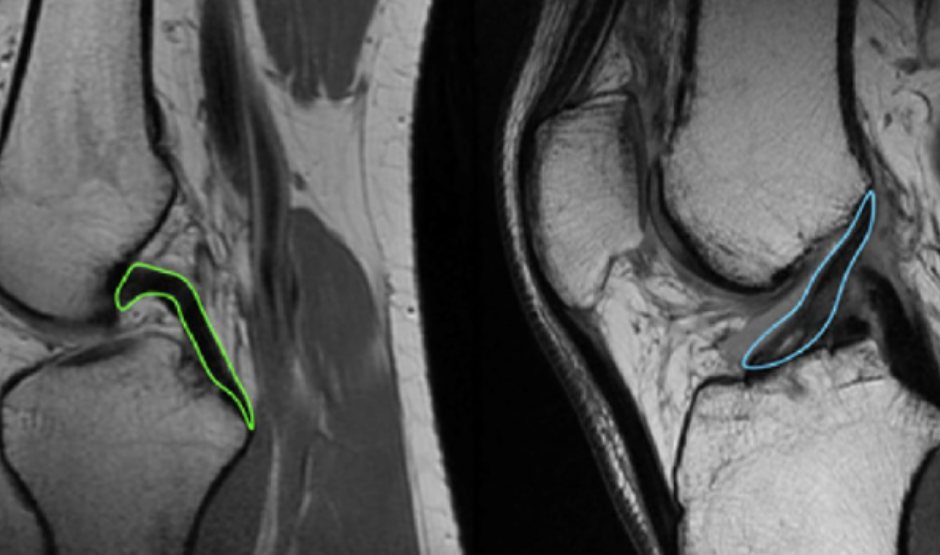

Peut-on réopérer un ligament croisé déjà opéré ?

Il est tout à fait possible de réopérer un ligament croisé antérieur (LCA) déjà opéré, par ce qu’on appelle une reconstruction itérative ou une reprise chirurgicale. Cette intervention concerne une minorité de patients — entre 1,8% et 10,4% des cas selon la littérature